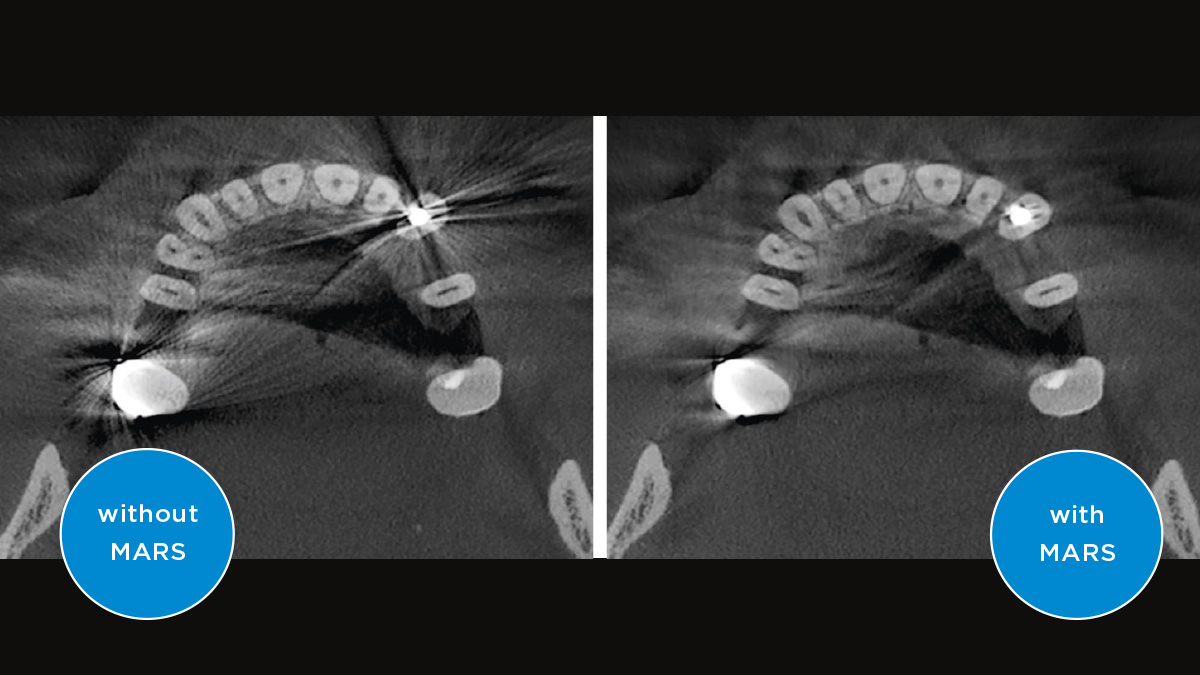

The high-quality 2D/3D X-ray device with a comprehensive range of services for every practice. Whether as a pure 2D device or including a 3D module – the Orthophos S is a reliable partner and optimized for everyday tasks. Its CsI Plus sensor with autofocus function ensures clear images, even in anatomically difficult cases. The automatic patient positioning together with the patented occlusal bite block enables an easy and timesaving patient positioning. For use in orthodontics, the Orthophos S is also available with an optional ceph arm. And because future-proofing is important to Dentsply Sirona, the cephalometric arm can be retrofitted at any time.

Even in anatomically difficult cases with the 2D CsI sensor with autofocus function